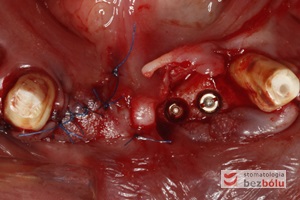

Wprowadzenie 4 implantów w odcinku przednim żuchwy